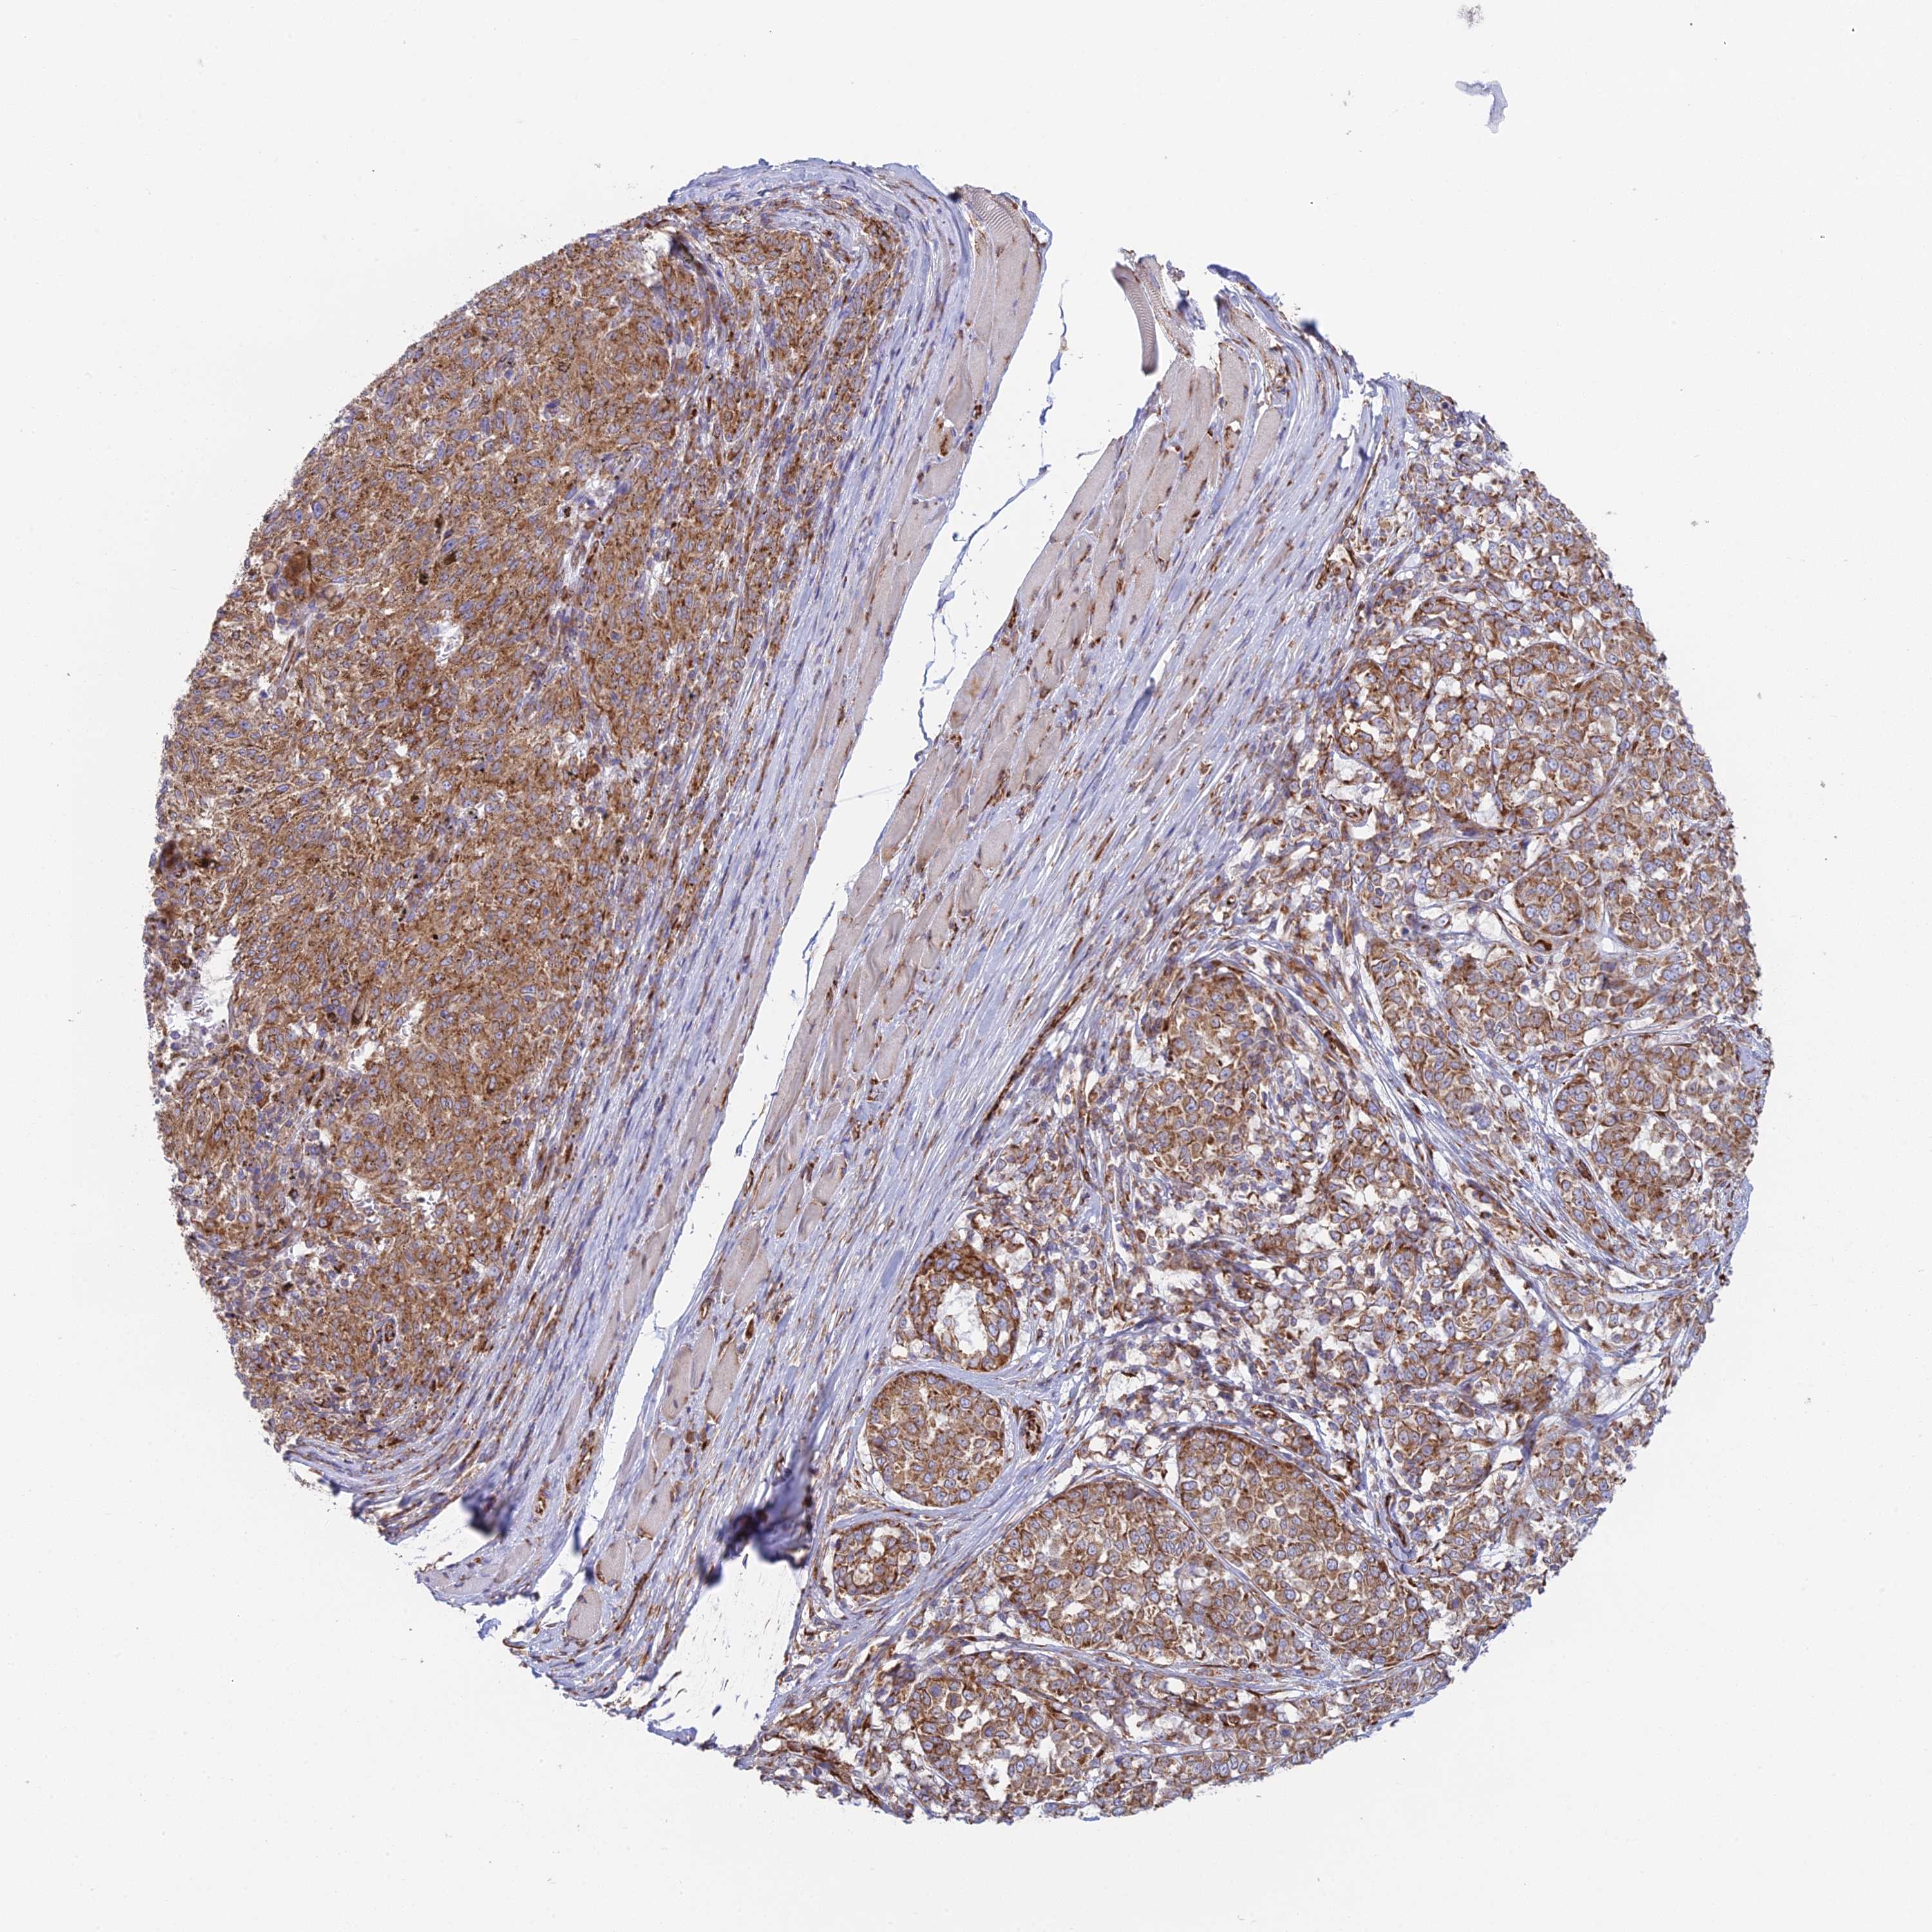

MELANOMA - Protein expressioni

A mouse-over function shows sample information and annotation data. Click on an image to view it in a full screen mode. Samples can be filtered based on level of antibody staining by selecting one or several of the following categories: high, medium, low and not detected. The assay and annotation is described here.

Note that samples used for immunohistochemistry by the Human Protein Atlas do not correspond to samples in the TCGA dataset.

Antibody stainingi

Antibody staining in the annotated cell types in the current human tissue is reported as not detected, low, medium, or high, based on conventional immunohistochemistry profiling in selected tissues. This score is based on the combination of the staining intensity and fraction of stained cells.

Each image is clickable and will lead to virtual microscopy that enables deeper exploration of all samples and also displays staining intensity scores, fraction scores and subcellular localization as well as patient and tissue information for each sample.

Antibody HPA043648

Staining

High

Medium

Low

Not detected

Intensity

Strong

Moderate

Weak

Negative

Quantity

>75%

75%-25%

<25%

None

Location

Nuclear

Cytoplasmic/membranous

Cytoplasmic/membranous,nuclear

Malignant melanoma, NOS

Malignant melanoma, Metastatic site